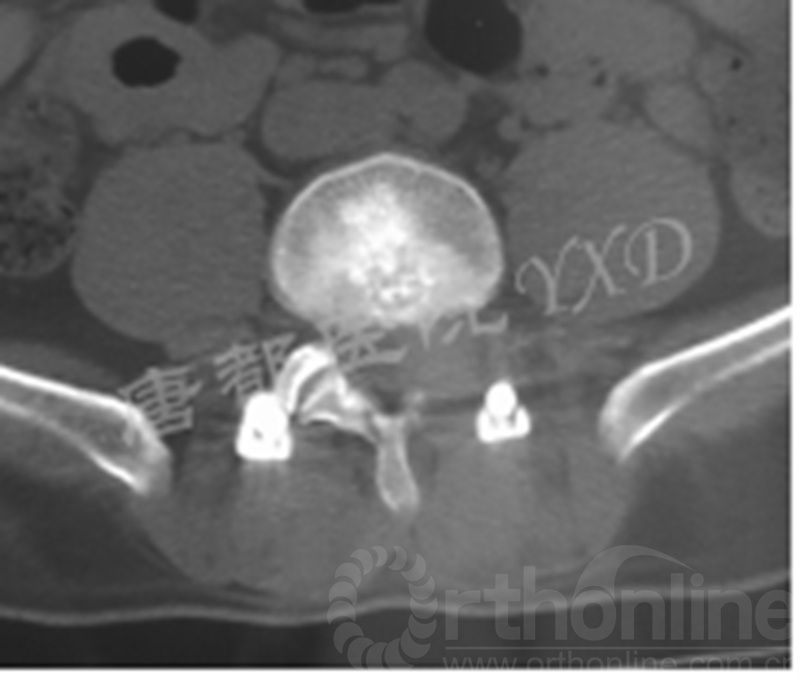

患者47岁,男性。

主诉:腰椎术后左下肢疼痛2月。

专科情况:跛行入病房;左侧直腿抬高试验阳性(60°)、加强试验阳性;左侧足背伸肌力、踇趾背伸肌力3级;左小腿外侧及足背皮肤感觉明显减退;余未见明显异常。VAS评分:左下肢7~8。

既往于半年前因“腰椎间盘突出症(L4-5)”于外院行腰椎侧路脊柱内镜下髓核摘除术(L4-5)。后因症状复发,分别在2周前、10天前于外院行两次腰椎后路脊柱内镜下髓核摘除术(L4-5)。

影像学检查:

诊断:腰椎间盘突出症术后复发

手术方案:显微镜辅助MI-TLIF腰椎翻修术

术中视频:http://api.orthonline.com.cn/attach/Case2.mp4(术中发现因前三次侧路及后路内镜手术的操作,术区大量瘢痕组织增生、与神经粘连严重;此外,摘除头侧游离髓核时连接有软骨终板脱落;在显微镜操作下,安全地将神经进行充分松解,压迫神经的游离髓核及软骨终板彻底清除。无手术并发症)

术后疗效:VAS评分左下肢1;左侧足背伸肌力、踇趾背伸肌力4级;左侧直腿抬高试验、加强试验阴性;行走自如、步态正常。